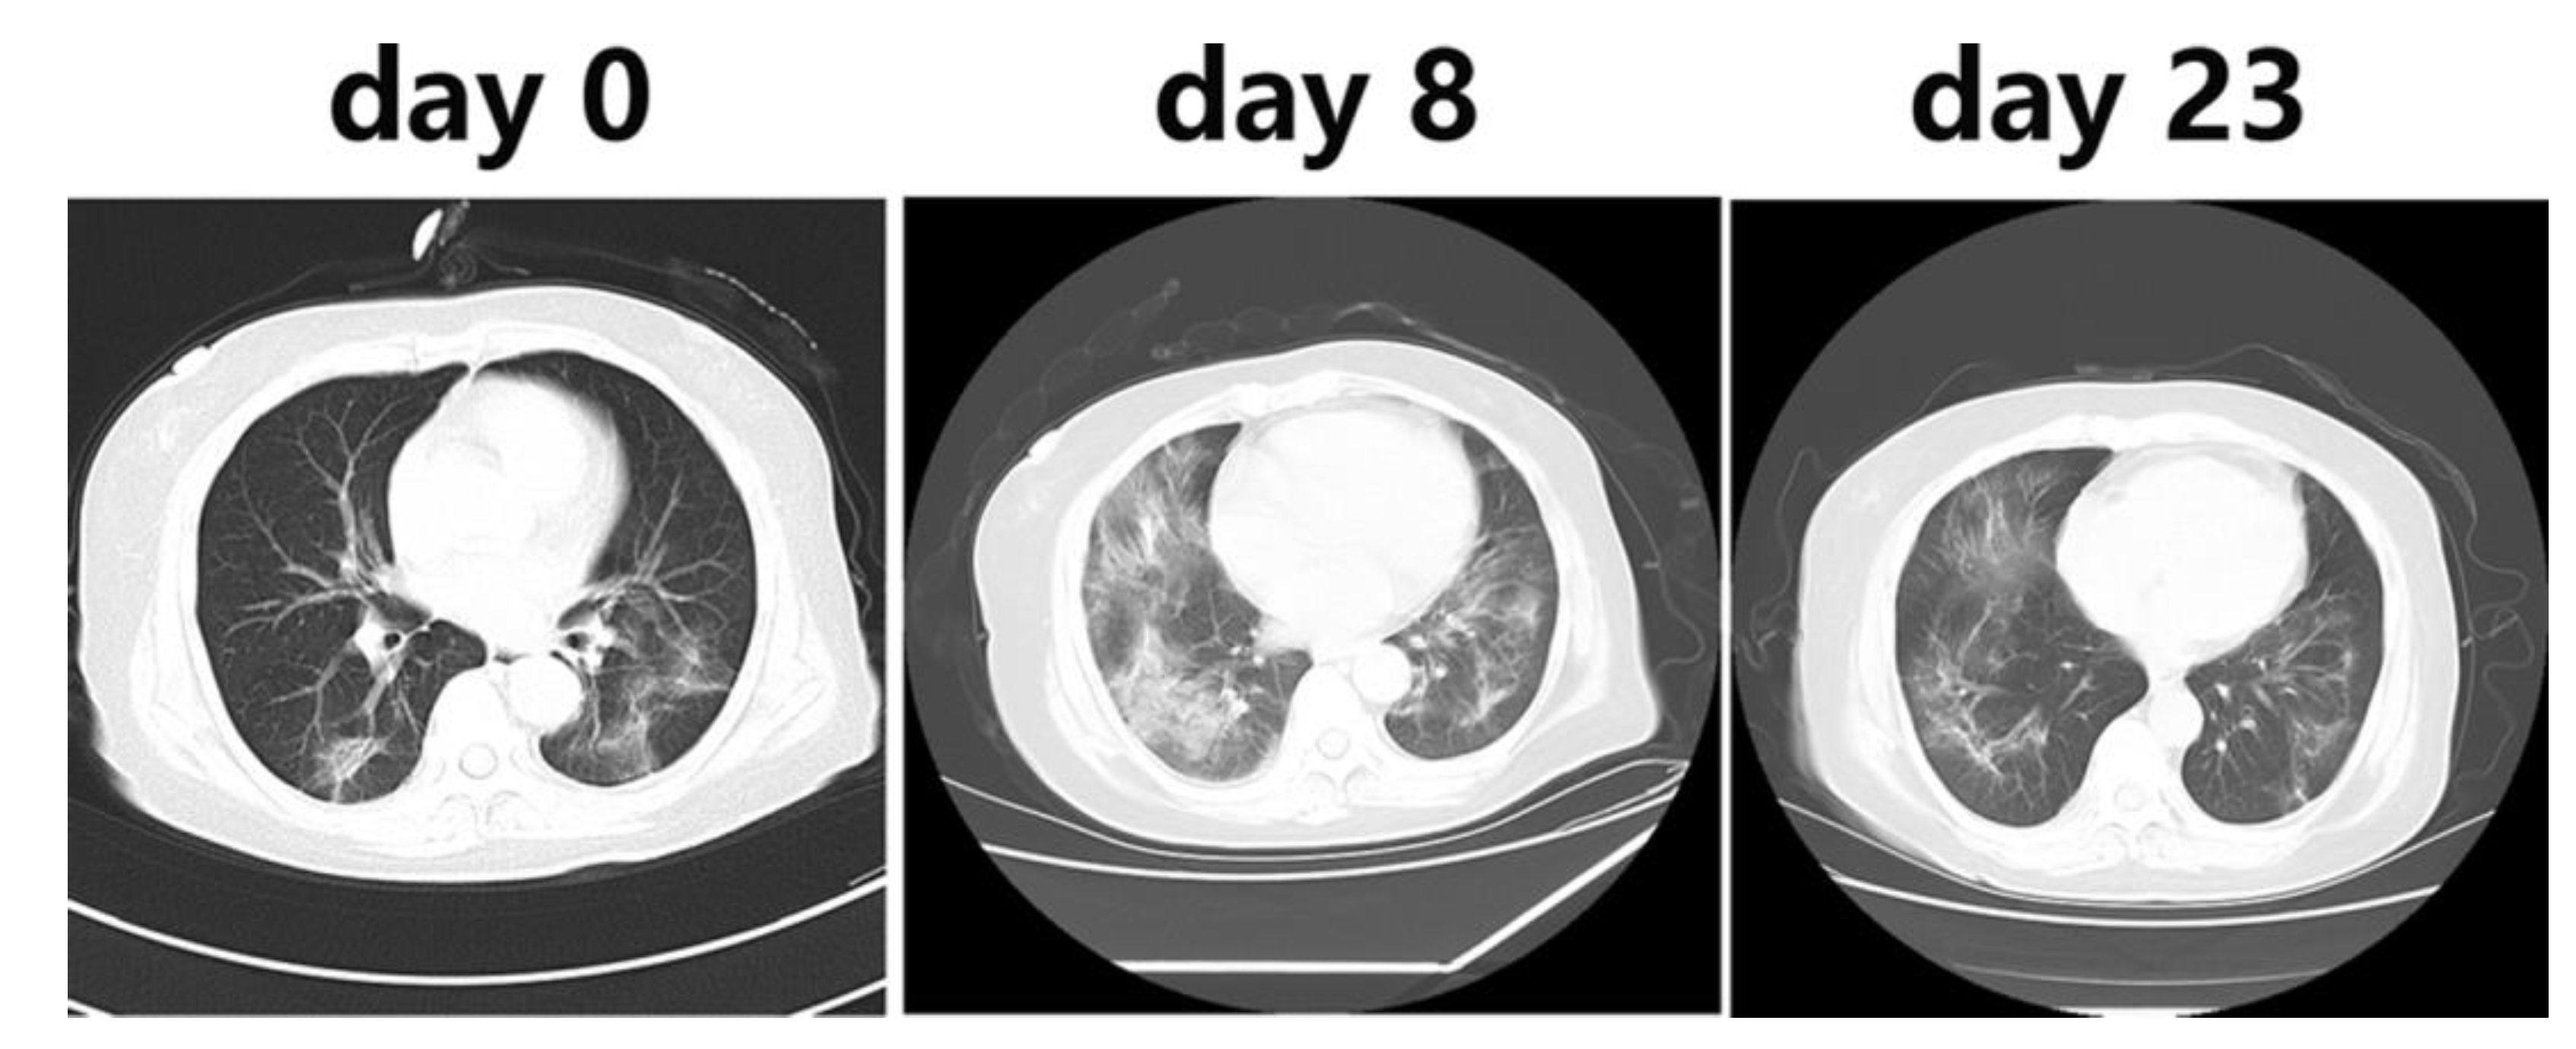

Besides, R. Li et al [8] used the CT imaging for the detection of COVID-19, they reported that the CT scans of all COVID-19 patients showed lung infiltrates and for 86.22%, multiple patchy glassy shadows were observed in the CT images of their both lungs. They also noted that the lesions increased by the progression of the disease and their scope in size or number expanded (Figure 2). In addition, N. Zhu et al [16] reported that the bilateral fluffy opacities were observed in the CT images of the lungs of a COVID-19 patient after 8 days of onset of symptoms but density, profusion, and the confluence of these bilateral fluffy opacities were increased by the progression of COVID-19 (after 14 days). Also, C. Huang et al. [5] noted that chest CT images of a 40-year-old man with COVID-19 recorded on day 15 after symptom onset showed sub-segmental areas of consolidation and bilateral multiple lobular while the images of a woman (53-year-old) recorded on 8th day after symptom onset showed sub-segmental areas of consolidation and bilateral ground-glass opacity and her CT image recorded after 12 days from symptom onset showed only bilateral ground-glass opacity. Based on the above-mentioned reports, the CT imaging method can be used as a highly accurate method for the clinical diagnosis of the COIVD-19 along with the rRT-PCR.

Figure 2. Chest CT images after 0, 8, and 23 days of onset of COVID-19 (adopted from R. Li et al., 2020 [8]).